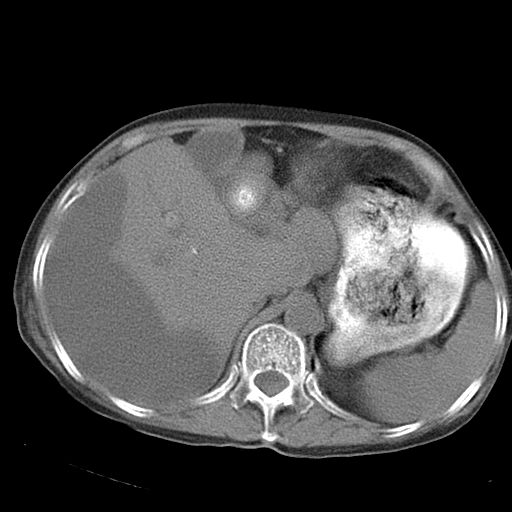

以下是引用dyqct在2006-12-7 21:08:00的发言:[br]考虑:1、肝内外胆管多发性结石伴肝左叶外侧段肝萎缩;[br] 2、右膈下多发脓肿;[br] 3、右侧少量胸腔积液、斜裂积液;[br] 4、左肾囊肿。

以下是引用jiazh在2006-12-7 20:37:00的发言:[br]肝脏周围半狐形低密度影,肝脏表面受压推移,考虑膈下脓肿可能性大;2、右侧胸腔积液

以下是引用拾荒者在2006-12-7 21:44:00的发言:[br]肝内外胆管多发结石,右膈下多发脓肿,右胸膜腔及叶间裂积液,左肾囊肿。[br] [br]